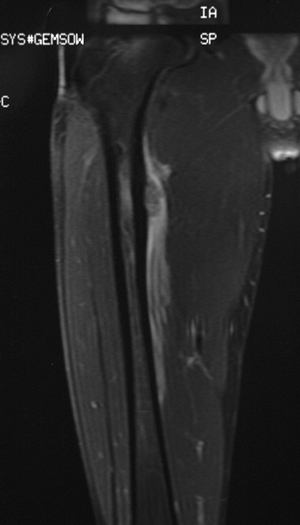

Figure 6.2-6

Magnetic resonance imaging shows large area of soft tissue involvement

without a stress fracture. This was diagnosed as a Ewing sarcoma of

bone and was treated with chemotherapy, wide resection, and bone

grafting. -